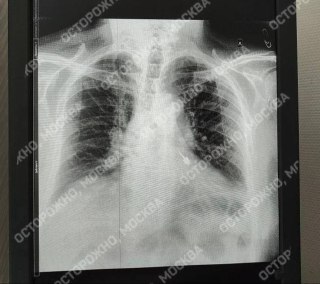

Пациент обратился за лечением зубов в частную клинику, и в какой-то момент в его дыхательные пути попал бур. К счастью, он быстро добрался до больницы в Мытищах, где рентген показал, что инструмент застрял в бронхе.

Врачи провели срочную операцию, аккуратно извлекли бур эндоскопическим инструментом, чтобы не повредить ткани. Всё прошло успешно.